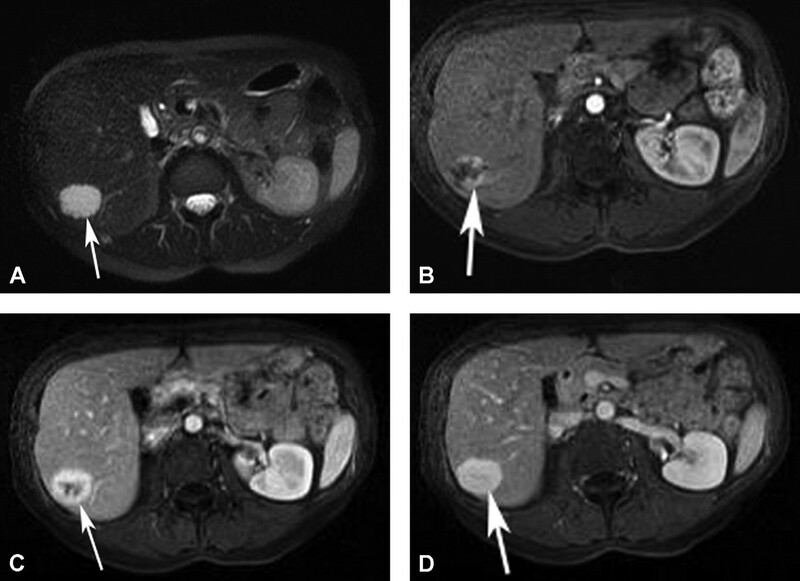

Hemangioma là u gan lành tính thường gặp nhất. Hemangioma thường gặp ở phụ nữ trẻ và 15-20% nhiều ổ. Mô học cho thấy một loạt các hồ máu và kênh mạch, các tổn thương lớn hơn tạo ra các vùng huyết khối và xơ. Siêu âm thấy một khối tăng âm, đồng nhất, giới hạn rõ, tăng âm phía sau yếu (Hình 1). Các tổn thương lớn hơn (>6cm) có thể không đồng nhất và giảm âm do huyết khối, hoại tử và thoái hóa nang. Các dấu hiệu CT cản quang gồm tăng quang dạng nốt ngoại vi ở thì động mạch với lấp đầy hướng tâm dần trong tổn thương ở thì tĩnh mạch cửa và thì muộn (hình 2). Vôi tĩnh mạch (phlebolith) có thể thấy trong tổn thương ở 15-20% trường hợp (Hình 2). MRI cho thấy tăng tín hiệu trung bình trên T2W, thường ít hơn so với nang đơn thuần, tín hiệu thấp trên T1W. MRI sau tiêm thuốc cho thấy bắt thuốc dạng nốt gián đoạn phía ngoại vi ở thì động mạch, đó là đặc điểm điển hình của hemangioma (Hình 3). MRI thì tĩnh mạch và thì muộn có thể thấy các nốt bắt thuốc lớn dần và hợp lưu với lấp dầy trung tâm ở các mức độ khác nhau tương tự như CT.

Hình 3. Hemangioma gan kinh điển. Tổn thương (mũi tên) tăng tín hiệu trên T2W FS single-shot fast spin-echo(SSFSE) (A). Có bắt thuốc dạng nốt ngoại vi (mũi tên) ở thì động mạch (B) và lấp dần vào trung tâm (mũi tên) ở thì tĩnh mạch cửa (C) và thì muộn (D) trên hình T1W 3D GRE.